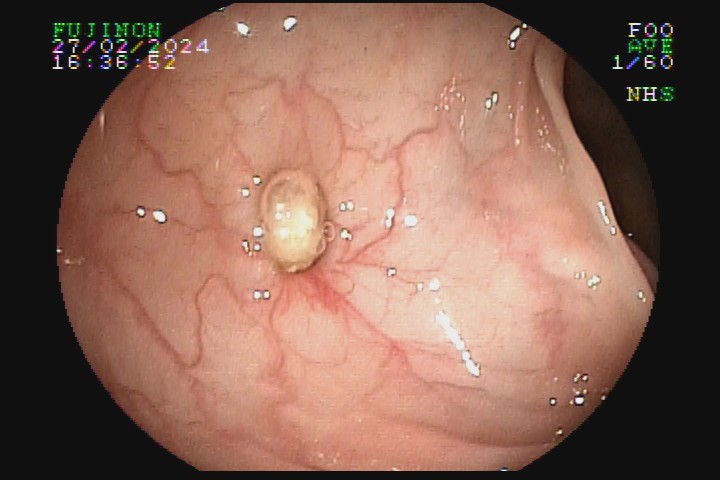

A diverticulose é uma doença adquirida, frequente entre pessoas mais idosas. Acredita-se que tenha como principal fator etiológico hábitos dietéticos relacionados com o refinamento da dieta industrializada. Pode ter uma evolução benigna por toda a vida e ser totalmente assintomática, mas pode também caracterizar-se como doença de sinais e sintomas agressivvos, com considerável morbidade e mortalidade devido às suas principais complicações: inflamação e sangramento.

A diverticulose cólica é consequência da herniação da mucosa do intestino grosso por entre as fibras musculares da parede intestinal. A diverticulose do cólon esquerdo complica mais com inflamação, e a diverticulose do cólon direito complica mais com sangramento.